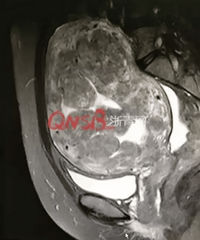

每次来例假都用掉三四包卫生巾,医生打开她的子宫后惊呆了!

阅读:2.2万回复:15